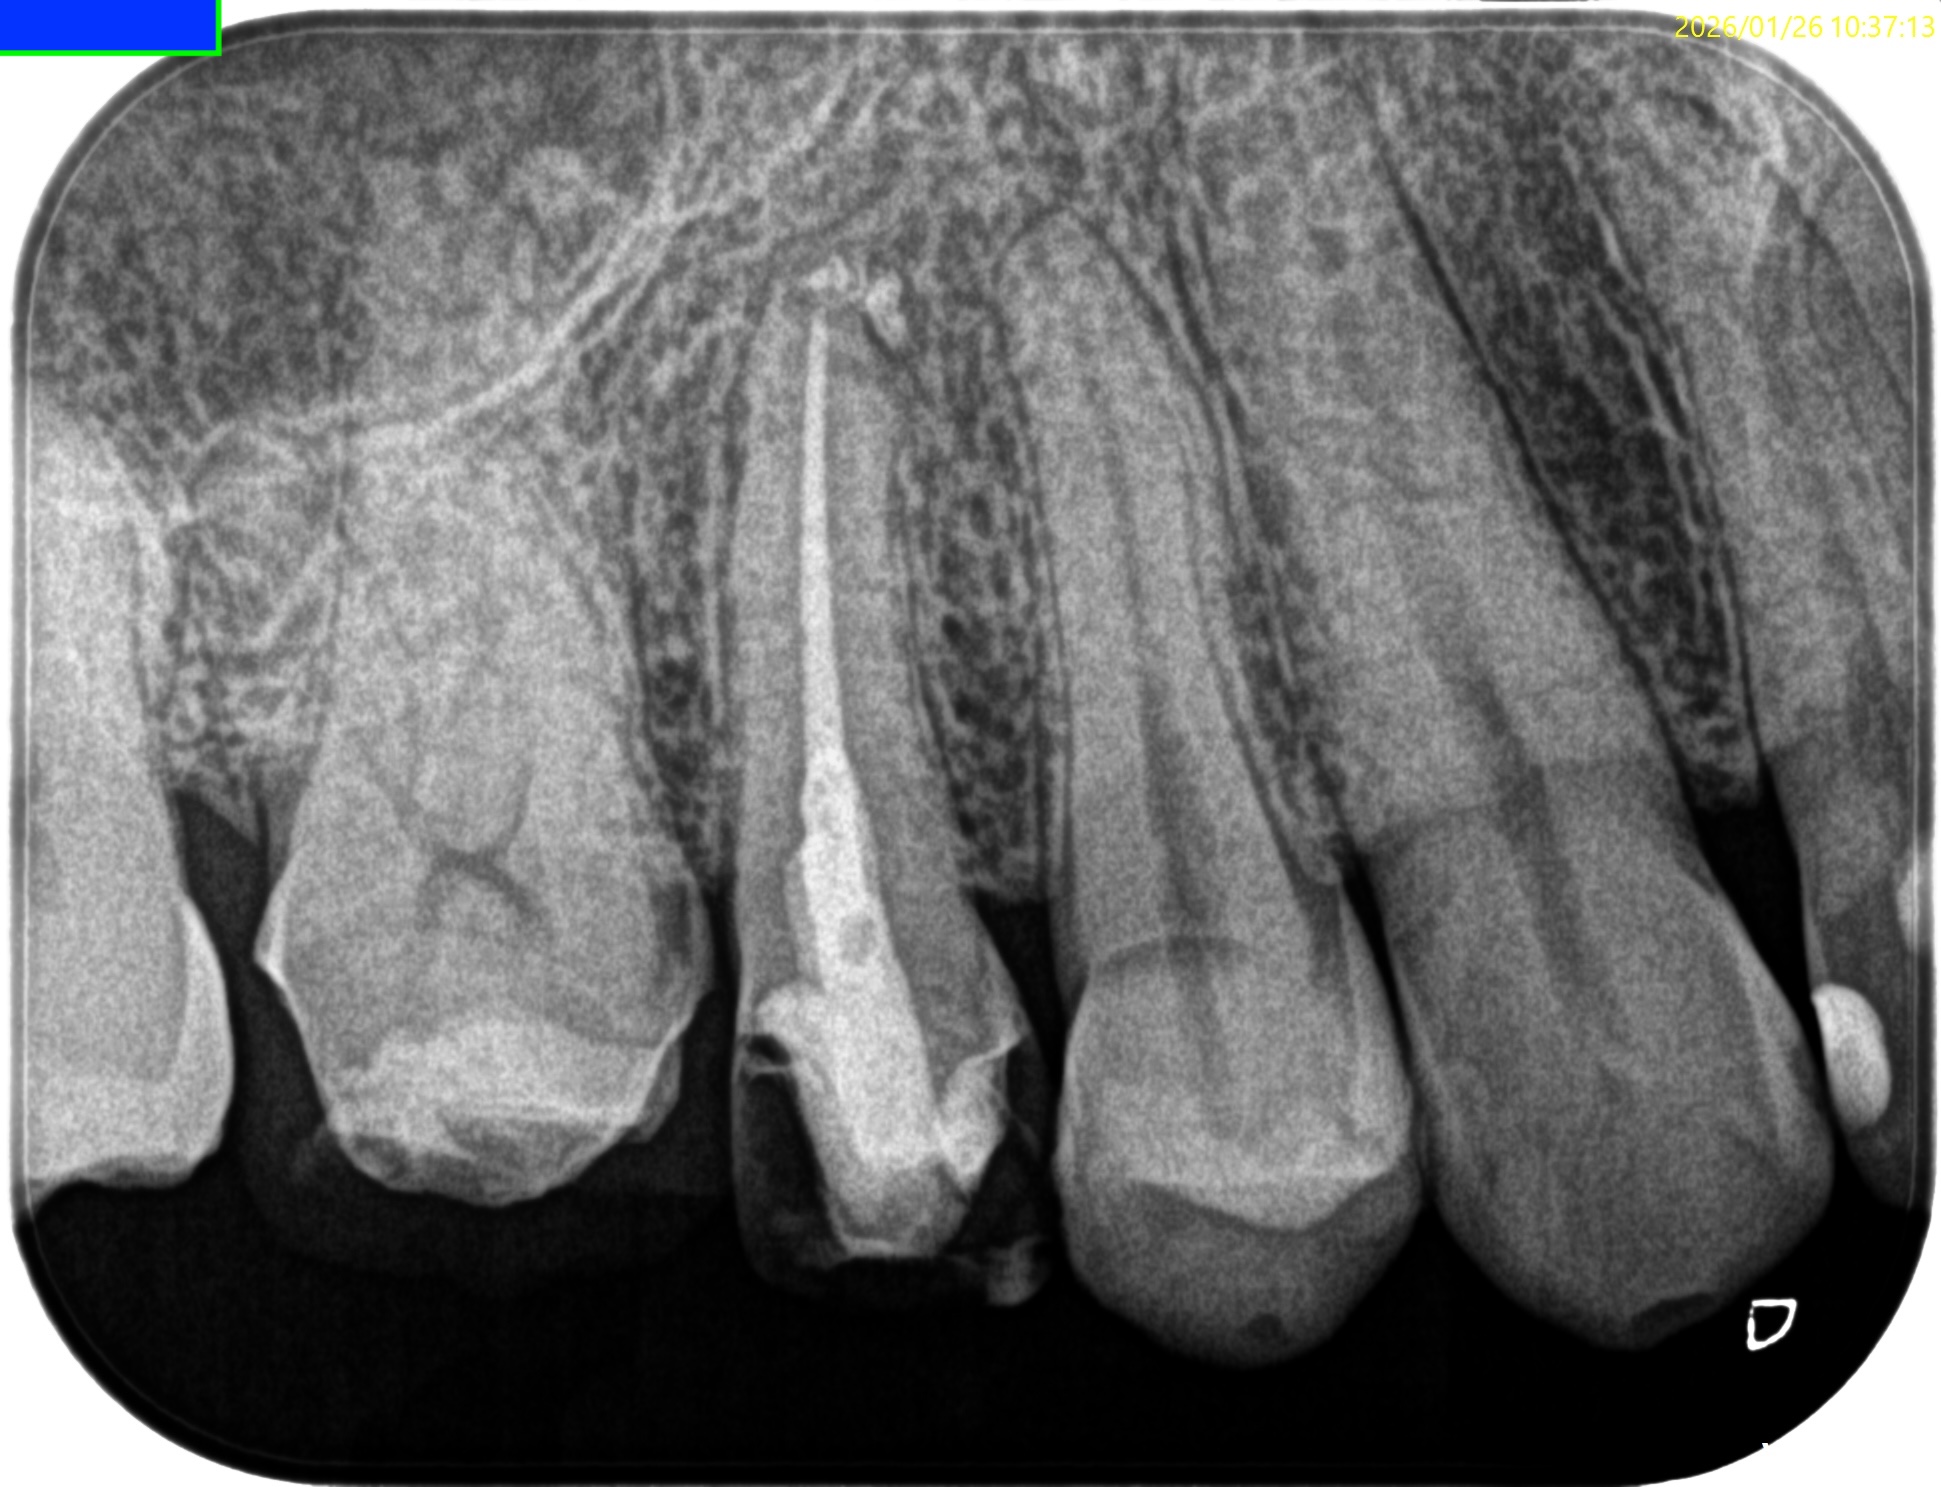

#4 RCT 8M recall(2026.1.26)

初診時と比較した。

根尖病変はほぼ消失した。

最終補綴もOKである。